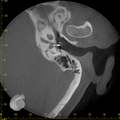

Ambossarrosion mit Stapesprothese Stapesprothese Teflon (Causse) PORP auf Stapes PORP Titan auf Stapes PORP PORP Titan disloziiert Otosklerose Otoskleroseherd TORP Pauke nicht belüftet TORP unter Knorpelinsel disl.